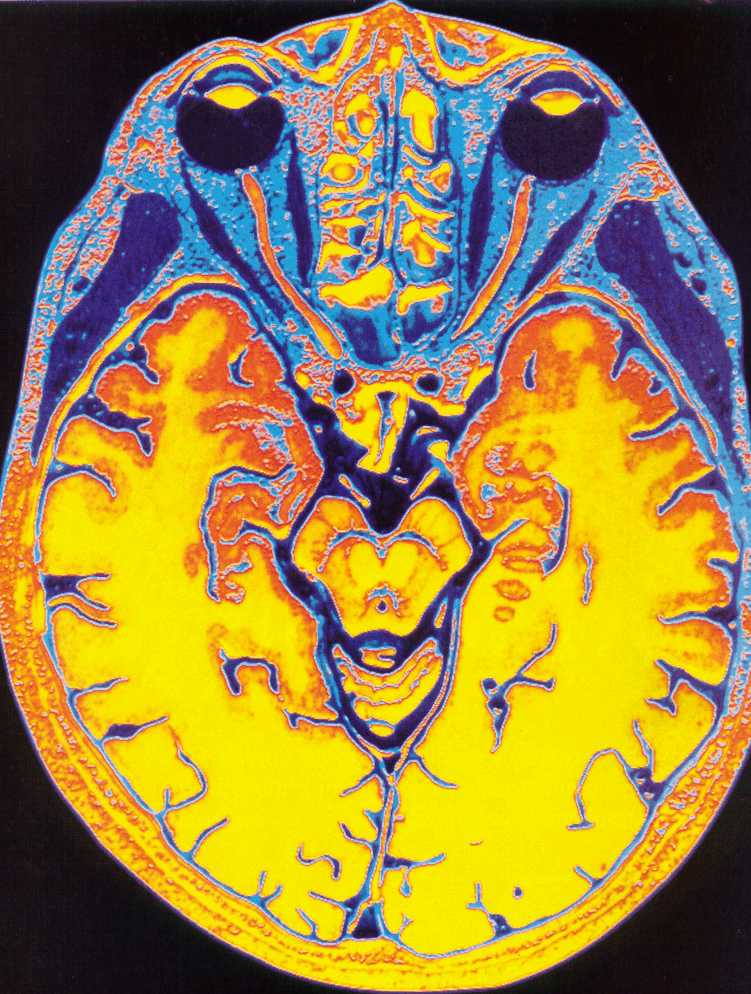

Если вы не знакомы с этим тестом, МРТ использует магнитное поле и радиоволны, чтобы сделать подробные снимки ваших внутренностей.

По данным клиники Мэйо, когда вы находитесь внутри аппарата МРТ, его магнитное поле временно перестраивает атомы водорода в вашем теле. Радиоволны заставляют эти атомы создавать очень слабые сигналы, которые используются для создания изображений поперечного сечения.Эти изображения накладываются друг на друга, чтобы врачам было действительно хорошо видно ваше тело изнутри, которое они могут видеть под разными углами.

«Он обеспечивает отличную анатомическую детализацию мягких тканей, что полезно для оценки конкретных условий», — объясняет она.

По данным клиники Майо, МРТ позволяет выявить широкий спектр проблем, включая аномалии дисков в позвоночнике, проблемы с суставами, опухоли в различных органах, таких как почки и яичники, структурные проблемы в сердце и травмы головного мозга.